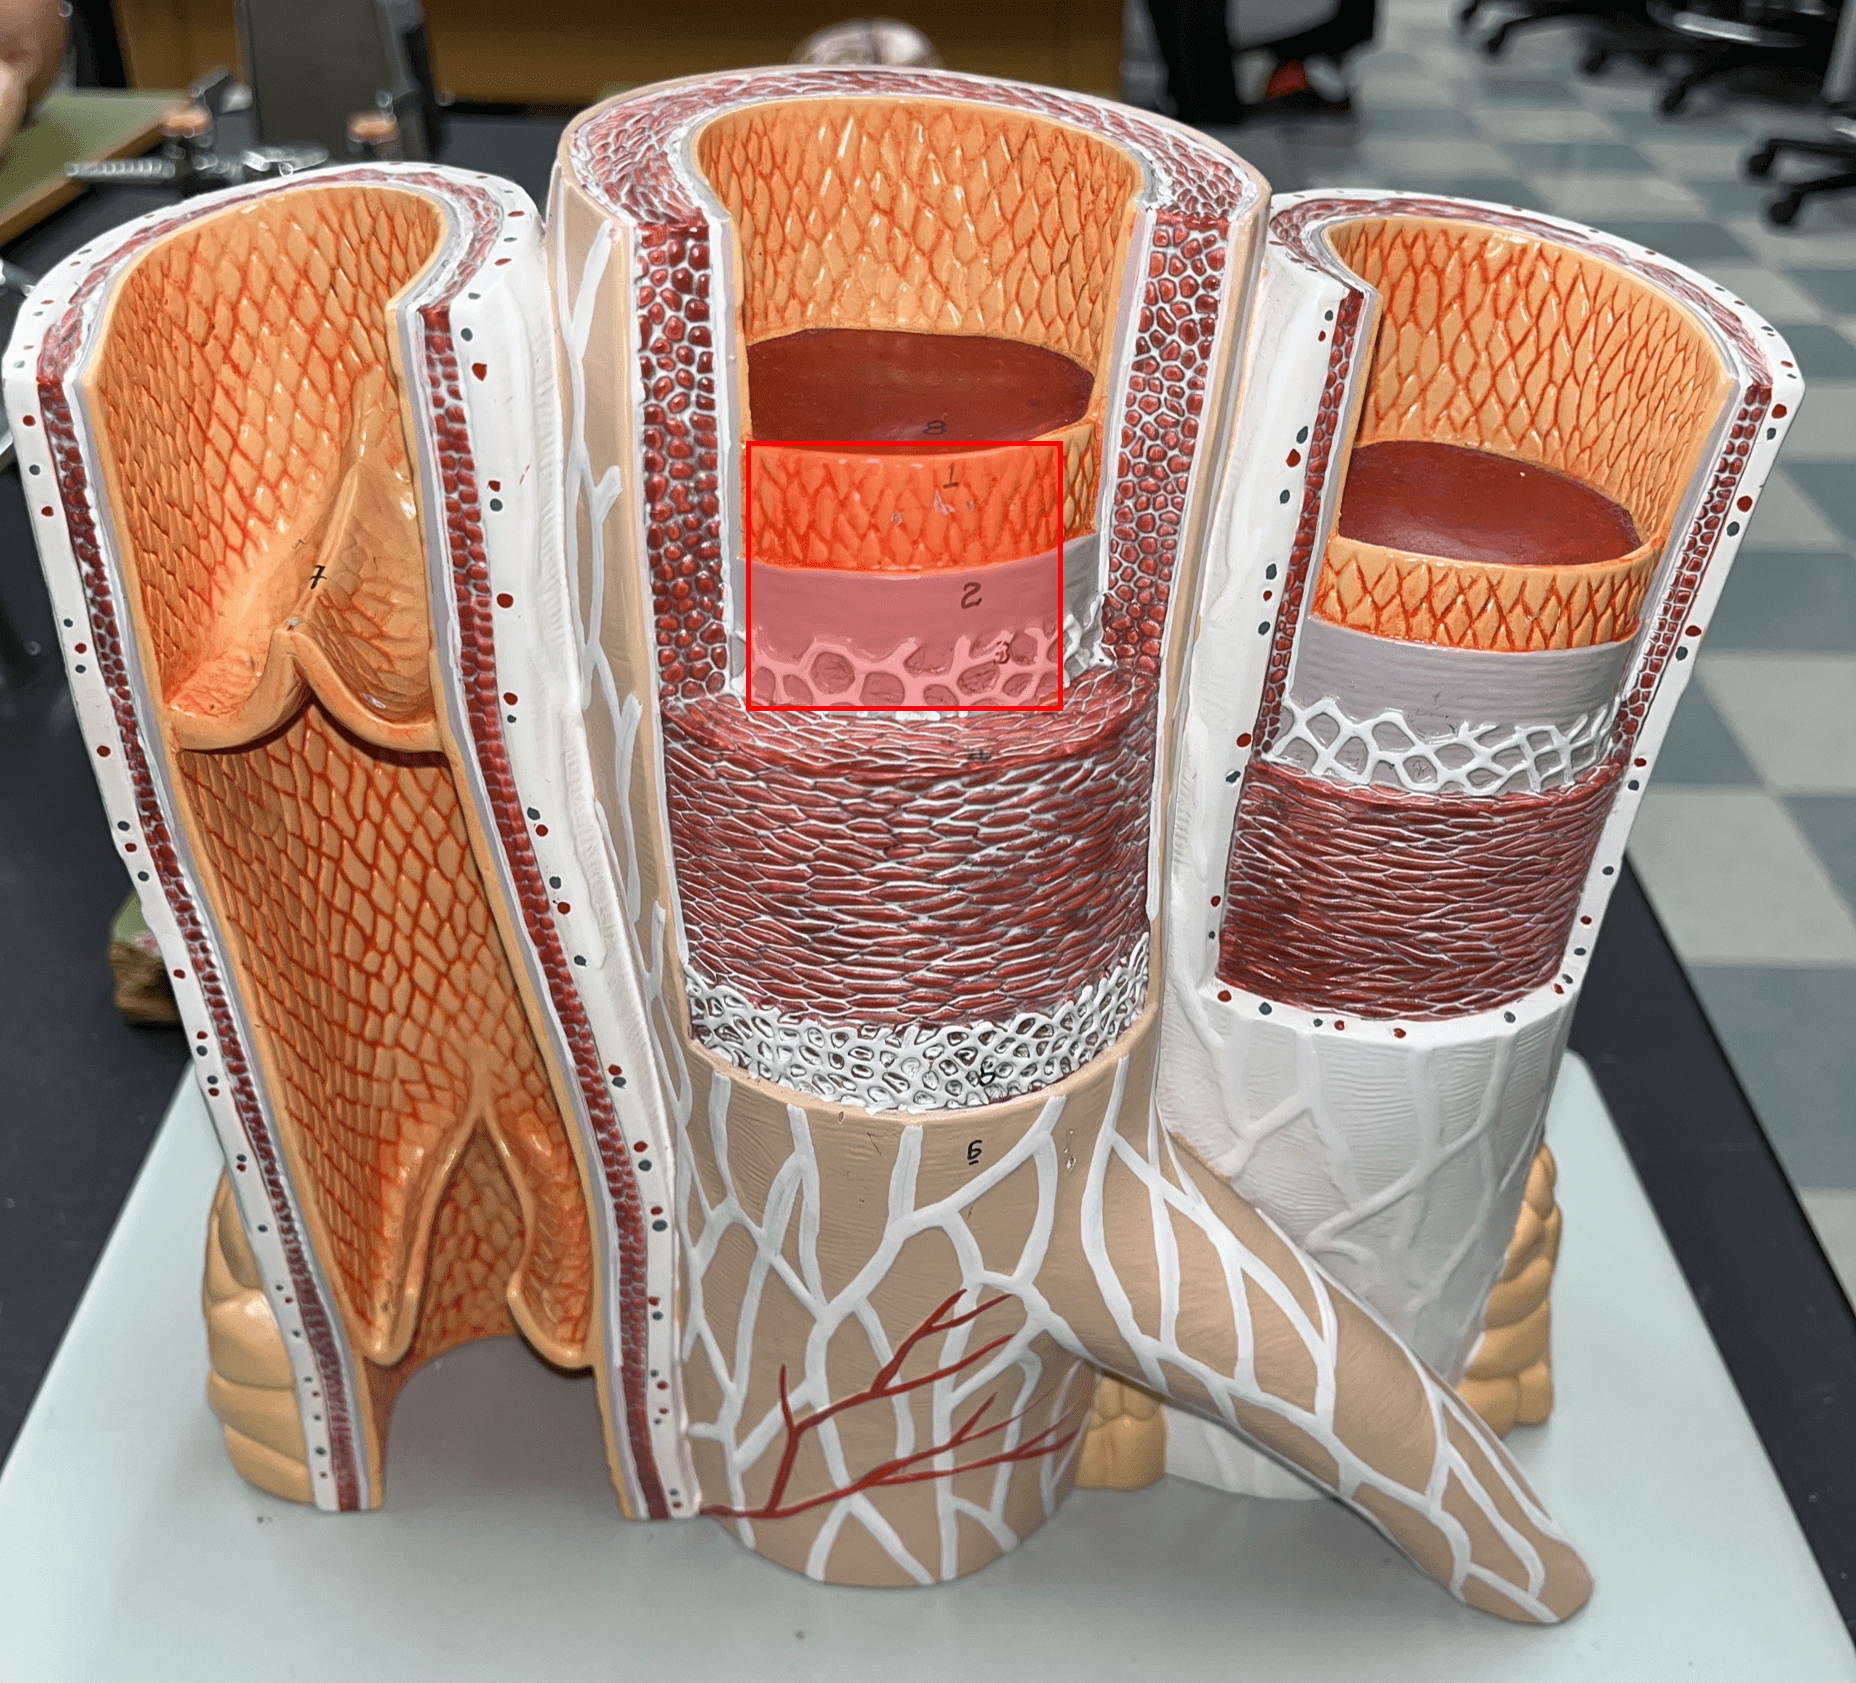

10

New cards

tunica interna

• The innermost layer of an artery.

• Consists of an inner endothelium and an outer basement membrane.

• Also known as the tunica intima.

• Consists of an inner endothelium and an outer basement membrane.

• Also known as the tunica intima.